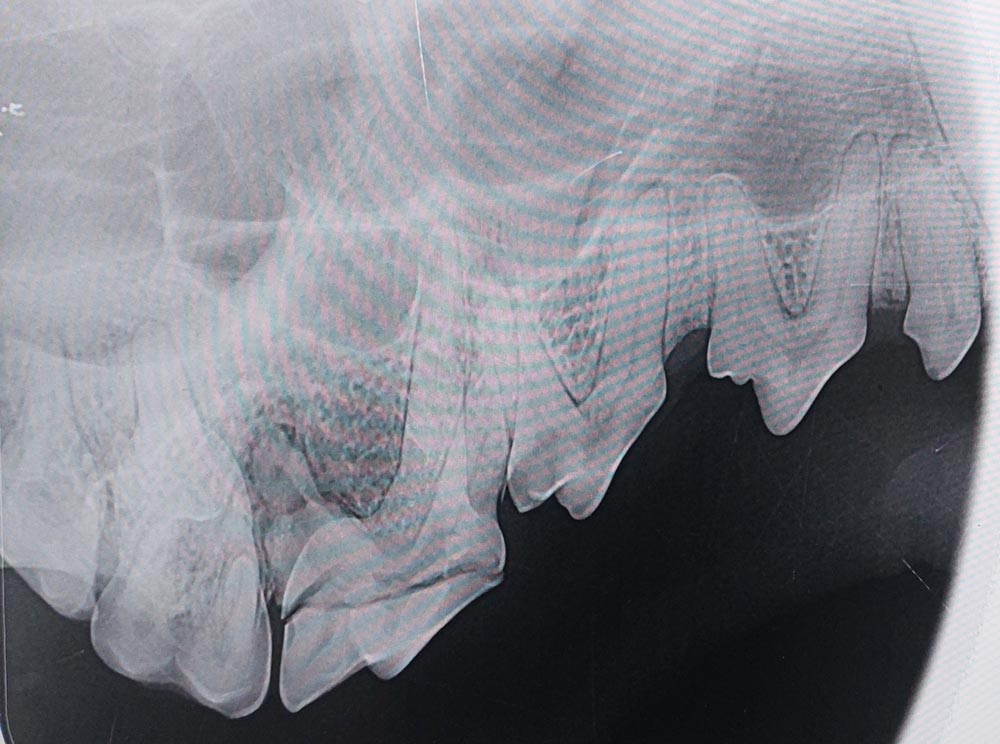

Das intraorale Dentalröntgen, auch einfach Zahnröntgen genannt, ist ein unverzichtbarer Baustein einer guten Zahnbehandlung. Es ermöglicht uns das rasche Anfertigen von hochwertigen Dentalröntgenbildern sowohl der Einzelzähne mit ihren Wurzeln als auch des Kiefers. Ein Großteil der krankhaften Veränderungen befindet sich im äußerlich nicht sichtbaren Bereichen der Wurzel und des Zahnhalses.

Hierzu gehören vor allem die resorptiven Läsionen bei Katzen (auch bekannt als FORL) oder die Wurzelspitzenabszesse der Eckzähne bei Hunden. Diese Befunde können nur über bildgebende Verfahren korrekt erfasst werden.